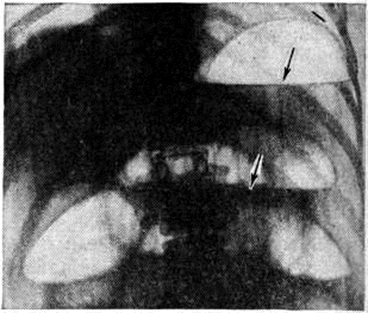

Механическая Непроходимость кишечника может быть обтурационной, странгуляционной и сочетанной. При обтурационной непроходимости закрывается только просвет кишечной трубки, а кровоснабжение её первоначально не страдает, поскольку сосуды брыжейки не подвергаются сдавлению. При странгуляционной Непроходимость кишечника не только нарушается пассаж по кишечнику, но и происходит сдавление, ущемление и перекручивание сосудов брыжейки, вследствие чего развивается некроз стенки кишки. Сочетанные формы Непроходимость кишечника являются промежуточными между обтурационной и странгуляционной непроходимостью. К ним относятся инвагинация, при которой сосуды брыжейки не всегда и не сразу оказываются сдавленными, а также некоторые виды спаечной непроходимости. Динамическая Непроходимость кишечника возникает вследствие нарушения функциональный состояния кишечника; её разделяют на спастическую и паралитическую. Наиболее полно особенности Непроходимость кишечника отражает классификация, основанная на четырёх признаках: 1) происхождение, 2) механизм возникновения, 3) состояние кровообращения стенки кишки, 4) клинические, течение. По происхождению выделяют Непроходимость кишечника врождённую и приобретённую; по механизму возникновения — Непроходимость кишечника механическую и динамическую; по состоянию кровообращения кишечной стенки различают: Непроходимость кишечника обтурационную — на почве закупорки кишки опухолью, каловыми и желчными камнями, инородным телом, клубком аскарид (эти причины вызывают так называемый внутрикишечную непроходимость в отличие от внекишечной — вследствие сдавления кишки извне опухолью, гематомой и другие), иногда вследствие рубцового сужения, перегиба или перетяжки кишки спайкой, не сдавливающей брыжейку; странгуляционную — заворот, узлообразование, перетяжка кишки и брыжейки спайкой или другим тяжем, ущемление их в грыжевых воротах при внутренних или наружных грыжах живота; сочетанную — инвагинация, отдельные формы спаечной непроходимости. По клинические, течению выделяют частичную, полную (острая, подострая, хроническая, рецидивирующая), высокую и низкую Непроходимость кишечника СтатистикаПо данным В. И. Стручкова (1955), Д. П. Чухриенко (1958), Д. А. Арапова (1966, 1971), Г. М. Щекотова (1966), А. Е. Норенберг-Чарквиани (1969), острая Непроходимость кишечника составляет 3,5— 9, 4% всех острых заболеваний органов брюшной полости. При этом у 40% больных наблюдается динамическая, а у 60%— механическая форма непроходимости. В 75—80% случаев причиной возникновения механической непроходимости являются спайки в брюшной полости, а в 20—25% случаев — опухоли, врождённые и приобретённые изменения брыжейки, желчные и пищевые конкременты, рубцовое сужение кишки. В 30—45% случаев спайки брюшной полости вызывают функциональную — динамическую форму Непроходимость кишечника По данным К. С. Симоняна (1961), Д. А. Арапова и В. В. Уманской (1971), механическая Непроходимость кишечника встречается с частотой: странгуляционная — в 74% случаев (в том числе спаечная составляет 82,5%, заворот кишок — 12%, инвагинация — 3,5%, узлообразование —2%); обтурационная — в 26% случаев (в том числе опухолевая —61%, спаечная — 35%, закупорка инородными телами —4%). Этиология и патогенезПричины возникновения острой Непроходимость кишечника принято делить на производящие и предрасполагающие. Производящей причиной, как правило, являются остро развивающиеся нарушения моторной функции кишечника в виде гипер-, гипомоторных его реакций или сочетания одновременно появляющихся спазмов и параличей разных участков кишки. В редких случаях, при наличии предрасполагающих причин, производящей может явиться резкое повышение давления в брюшной полости, обусловленное физической нагрузкой или каким-либо другим фактором. Нарушение моторной функции кишечника может привести к развитию не только спастической и паралитической форм функциональный непроходимости, но и к завороту, узлообразованию, инвагинации, ущемлению кишки штрангом (тяжем), развитию обтурационного илеуса. Эти формы механической непроходимости обычно возникают при наличии предрасполагающих причин — врождённых или приобретённых анатомо-морфологических изменений в брюшной полости. К врождённым изменениям относят такие аномалии развития кишечника, брыжейки и брюшины, как мальротация, дивертикулёз, общая брыжейка слепой и подвздошной кишки, caecum mobile, долихосигма, а также дефекты развития диафрагмы и брюшины, приводящие к возникновению ворот, щелей, карманов в брюшной полости. К приобретённым изменениям, предрасполагающим к возникновению Непроходимость кишечника, относят: спайки, сращения, рубцовые тяжи, образующие отверстия и карманы в брюшине и брыжейке, возникшие как следствие воспалительного процесса или оперативного вмешательства в брюшной полости; опухоли, воспалительные инфильтраты, гематомы, исходящие из стенки кишки или окружающих её органов; наличие в просвете кишки инородных тел, желчных и каловых камней, глистов, больших кусков непереваренной пищи и так далее Причинами, предрасполагающими к возникновению как механической, так и динамической Непроходимость кишечника, являются изменения функциональный состояния тонкой кишки, обусловленные длительным голоданием (особенно с последующим перееданием), хронический воспалительными заболеваниями кишечника (колит и энтероколит), а также повреждением тканей кишки вследствие изменений регионарного кровообращения в кишечной стенке (например, при спаечной непроходимости). Хроническая Непроходимость кишечника чаще обусловлена спаечным процессом в брюшной полости после ранее перенесённых операций, травм и проникающих ранений живота, реже обтурация кишки возникает при медленно растущей опухоли. Форма возникшей Непроходимость кишечника зависит как от характера предрасполагающих причин, так и от вида нарушений моторной функции кишечника. Многочисленные экспериментальные исследования и клинические, наблюдения свидетельствуют о том, что и гипер и гипомоторные реакции, обусловливающие возникновение Непроходимость кишечника, являются результатом расстройств нервной регуляции двигательной активности кишечника. Эти расстройства могут быть вызваны повреждением тканей головного, спинного мозга и крупных стволов вегетативных нервов как вследствие механической травмы, сосудистых нарушений (инсульт, гематомы), воспалительных процессов (менингит), так и в результате экзо и эндогенных токсических воздействий (при отравлении свинцом, диабетической коме и так далее). Нарушение функций нервных центров, регулирующих двигательную активность кишечника, может быть обусловлено и чрезвычайным раздражением рецепторов внутренних органов при возникновении патологический процессов в них. Так, гипомоторные реакции кишечника могут быть следствием раздражения рецепторов брюшины при перитоните, травматичных операциях в брюшной полости или вне её (послеоперационные парезы и параличи кишечника), возникают при перерастяжении кишечника грубой пищей, при почечной и печёночной колике, всегда сопровождают повреждения и воспалительные процессы в забрюшинном пространстве. «Абдоминальная маска», то есть картина функциональный Непроходимость кишечника, может явиться следствием инфаркта миокарда, плеврита, гемоторакса, а у детей даже таких заболеваний, как грипп или отит (смотри полный свод знаний Псевдоабдоминальный синдром). Непосредственной причиной расстройств моторной функции кишки, вследствие которых возникает Непроходимость кишечника, является нарушение баланса симпатических и парасимпатических влияний на гладкие мышцы кишечной стенки. Преобладание парасимпатических влияний ведёт к возникновению гипермоторных форм нарушения двигательной активности в виде стойких спазмов кишки и резкого усиления её перистальтики; преобладание симпатических влияний вызывает гипомоторные реакции, выражающиеся в угнетении перистальтики и в возникновении парезов и параличей мышц кишечника. С момента появления препятствия, обусловливающего прекращение пассажа кишечного содержимого, остро возникшая Непроходимость кишечника становится начальным звеном в патогенезе патологический процесса, имеющего общие для разных форм непроходимости патогенетические механизмы. В начальной фазе (рефлекторной) заболевания ведущим становится нервнорефлекторный фактор. Степень возникающих нарушений центральная нервная система зависит от размеров поражённого рецепторного поля и локализации очага повреждения. Последнее определяется тем, что чувствительность рефлексогенных зон кишечника не одинакова в различных отделах. Наибольшей чувствительностью обладают рецепторы двенадцатиперстной кишки. При странгуляционной форме непроходимости и высокой локализации препятствия интенсивность воздействия на нервные центры настолько велика, что ведущим в клинические, картине становится шок (смотри полный свод знаний) с характерными для него острыми расстройствами гемодинамики и дыхания. При обтурационной и динамической непроходимости, особенно при паралитической форме, первоначальное воздействие патологический импульсов на центральная нервная система не столь велико. Однако и при этих формах заболевания возникающие нарушения функций нервных центров вызывают расстройства деятельности эндокринной системы, в частности системы гипоталамус — гипофиз — надпочечник, нарушение гематоэнцефалического барьера. Следствием расстройств нейрогормональной регуляции являются прогрессирующие нарушения вегетативных функций: гемодинамики, дыхания, деятельности органов пищеварительного тракта. Первым и наиболее очевидным проявлением илеуса является нарушение моторной функции кишечника, которое при всех формах острой Непроходимость кишечника, за исключением первичной паралитической, вначале носит гипермоторный характер. При этом периоды резкого усиления моторной функции совпадают с болевыми приступами. Продолжительность гипермоторных реакций, как правило, невелика: постепенно истощаясь, они сменяются угнетением моторной функции с последующим развитием пареза и паралича кишечника. При этом раздражение интероцепторов в области возникшей непроходимости нарастает в результате постепенного скопления в просвете кишечных петель жидкости и газов. Началом второй, токсической, фазы Непроходимость кишечника следует считать нарастающее растяжение кишечных петель вследствие скопления жидкости и газа выше возникшего препятствия, а при паралитической непроходимости — и всего участка кишки, моторная функция которого заторможена. Скапливающаяся жидкость состоит из пищевых масс, пищеварительных соков, а на более поздних этапах — и из плазмы. Основную часть кишечных газов составляет азот. Растяжение кишечных петель обусловлено не только прекращением эвакуации содержимого вследствие нарушения двигательной активности, но одновременно и возникающими расстройствами секреции пищеварительных желёз, а также нарушением переваривающей и всасывательной функции кишки, то есть развитием синдрома недостаточности функций кишечника (смотри полный свод знаний Кишечник, заболевания). Повышение внутрикишечного давления оказывает местное и рефлекторное действие. Местное действие сводится к нарушению оттока крови по венам кишечника, что ведёт к уменьшению, а затем и прекращению всасывания газа и жидкости и как следствие этого — к прогрессирующему растяжению кишечных петель и нарушению питания кишечной стенки. Результатом раздражения интероцепторов при повышении давления в кишке является рефлекторное угнетение моторной функции желудка и кишечника, усиление секреции желёз пищеварительного тракта, нарушение всасывания и повышение проницаемости сосудов со значительной транссудацией жидкости в просвет растянутых кишечных петель. Суммарное действие местных и рефлекторных факторов приводит к замыканию порочного круга: развившийся синдром недостаточности функций кишечника ведёт к растяжению кишечных петель, а растяжение стенок кишки — к прогрессированию этого синдрома. Возникшие нарушения функций тонкой кишки определяют расстройства межуточного обмена. Независимо от того, удаляется ли часть содержимого при рвоте или все остаётся в просвете растянутых кишечных петель, значительное количество воды, электролитов и питательных веществ оказывается выключенным из обмена. Возникает состояние, которое Нефрокальциноз Нефрокальциноз Самарин (1931) характеризовал как расстройство сокооборота, приводящее к глубоким нарушениям белкового и водно-солевого обмена и как следствие этого — к нарастающей интоксикации (смотри полный свод знаний). На фоне полного голодания в условиях повышенного катаболизма организм лишается в сутки не только 20—30 грамм белка и 3—4 грамм полипептидов, которые в норме усваиваются из пищеварительных соков, но и всего белка, содержащегося в транссудате, поступившем в просвет кишки. Количество белка, ежесуточно теряемого с мочой, может достигать 140 г, общее же количество безвозвратно теряемого белка превышает 300 г, что само по себе может явиться причиной гибели организма. Следствием расстройств сокооборота являются и значительные потери воды и электролитов, что ведёт к нарушению водно-солевого обмена (смотри полный свод знаний), сгущению крови и дегидратации тканей. По мере увеличения срока от момента возникновения непроходимости метаболические расстройства нарастают, так как в результате нейрогуморальных сдвигов катаболизм усиливается, а обычный путь поступления в кровь экзо и эндогенных питательных веществ оказывается блокированным. С того момента, как темп потерь питательных веществ начинает превышать возможности их компенсации за счёт мобилизации эндогенных запасов, возникает нарушение гомеостаза (смотри полный свод знаний) и развивается интоксикация. В механизме развития интоксикации принимают участие и другие факторы. Так, согласно теории, выдвинутой Амюсса (J. Z. Amussat), интоксикация при Непроходимость кишечника обусловлена воздействием токсического кишечного содержимого. Это представление в дальнейшем было развито многими исследователями, объяснившими токсический эффект всасыванием бактериальных токсинов, продуктов распада белка, некоторых биологически активных веществ. В механизме развития интоксикации существенную роль может играть и перитонит (смотри полный свод знаний), присоединяющийся на поздних этапах заболевания. Причиной его развития является повышение проницаемости истончённой в результате растяжения кишечной стенки, через которую проходят бактерии и их токсины. Замкнувшийся порочный круг (прогрессирование нарушений функций кишечника — нарастание метаболических расстройств и интоксикации — усугубление нарушения функций кишечника и так далее) переводит заболевание в заключительную, терминальную, фазу. Нарастающее увеличение объёма кишечных петель ведёт к повышению внутрибрюшного давления, уменьшению экскурсий диафрагмы и сдавлению средостения. Следствием этого является гипоксия (смотри полный свод знаний), обусловленная изменениями центральной гемодинамики и дыхания, а также усугубляющиеся расстройства регионарной циркуляции в кишечнике вследствие нарушения оттока по портокавальной системе. В терминальной фазе заболевания прогрессирующая недостаточность функций кишечника, ведущая к нарушению экзои эндогенного питания, обмена веществ и, в конечном счёте, постоянства состава внутренней среды организма, становится ведущим механизмом в танатогенезе Непроходимость кишечника Однако далеко не всегда летальный исход при Непроходимость кишечника обусловлен прогрессированием недостаточности функций кишечника. Так, причиной смерти больных со странгуляционной формой непроходимости может быть шок, приводящий к необратимым нарушениям постоянства газового состава внутренней среды и нарастающей гипоксии мозга. При любой форме Непроходимость кишечника тяжёлые нарушения деятельности нервных центров и регулируемых ими вегетативных функций могут привести к летальному исходу вследствие остро развившейся сердечно-сосудистой, дыхательной или почечно-печёночной недостаточности. Патологическая анатомияАнатомические изменения при странгуляционной Непроходимость кишечника выражаются в нарушении кровообращения и лимфооттока, альтеративно-деструктивных процессах и воспалительной реакции. Локализация, объем, степень и глубина этих процессов определяются длительностью заболевания. При непроходимости на почве ущемления петли кишки с брыжейкой, спаек, тяжей брюшной полости возникают наиболее резкие изменения ущемлённого отдела, странгуляционных борозд, а затем и приводящей петли (рисунок 1). Позднее изменяется дистальный отдел. Макроскопически ущемлённая петля кишки с первых часов заболевания принимает синюшно-красную окраску, через 20—24 часа становится почти чёрной, вздута, переполнена кровянистой жидкостью и газами. Стенка кишки отёчная, с расслаивающими и пятнистыми кровоизлияниями. Брыжейка с расширенными и тромбированными венами, множеством точечных кровоизлияний также отёчна. Микроскопически некроз (смотри полный свод знаний) начинается со слизистой оболочки противобрыжеечного края кишки. В первые 6 часов сохраняется лишь эпителий крипт, нарастает отёк подлежащих слоёв. Через 7—10 часов нарушается циркулярный мышечный слой. Изменения в местах странгуляционных борозд (рисунок 2, 3) по степени и глубине поражения проходят 5 стадий: 1) сдавление всех краёв с малокровием их; 2) размозжение, некроз слизистой оболочки, истончение подслизистой основы, деформация мышечных слоёв; 3) разрушение мышечных слоёв при сохранности брюшины; 4) преперфоративное состояние при отторжении погибших внутренних слоёв; 5) перфорация стенки кишки. Усиленная перистальтика в приводящем отделе кишки отмечается вначале, позже происходит паретическое расширение её просвета, на границе приводящего и ущемлённого участков кишки нарастает полнокровие вен, отёк, стаз. Эти изменения вначале занимают 2—3 сантиметров кишки, но через 24—48 часов распространяются на 30—40 сантиметров её приводящего отдела. Отводящий отдел кишки бледен, спастически сокращён. В брюшной полости накапливается геморрагическая жидкость. Воспалительная реакция начинается в стенке ущемлённого отдела через 6—12 часов, причём серозный покров вовлекается в патологический процесс через 10—12 часов Динамика изменений при ущемлённых грыжах идентична описанным, но степень поражения стенки в участках борозд ущемления нарастает медленнее. Большое значение имеет изучение морфологии кишечной стенки приводящего отдела тонкой кишки до и после устранения механического препятствия. Гистологическое и электронно-микроскопическое изучение эпителиального покрова кишечных ворсин слизистой оболочки тонкой кишки при экспериментальной Непроходимость кишечника и у больных со странгуляционной и спаечной Непроходимость кишечника выявило динамику структурных изменений каёмчатых энтероцитов, ответственных за функции всасывания, переваривания и синтез ферментов, а также изменения в системе микроциркуляторного русла стромы кишечной ворсины.